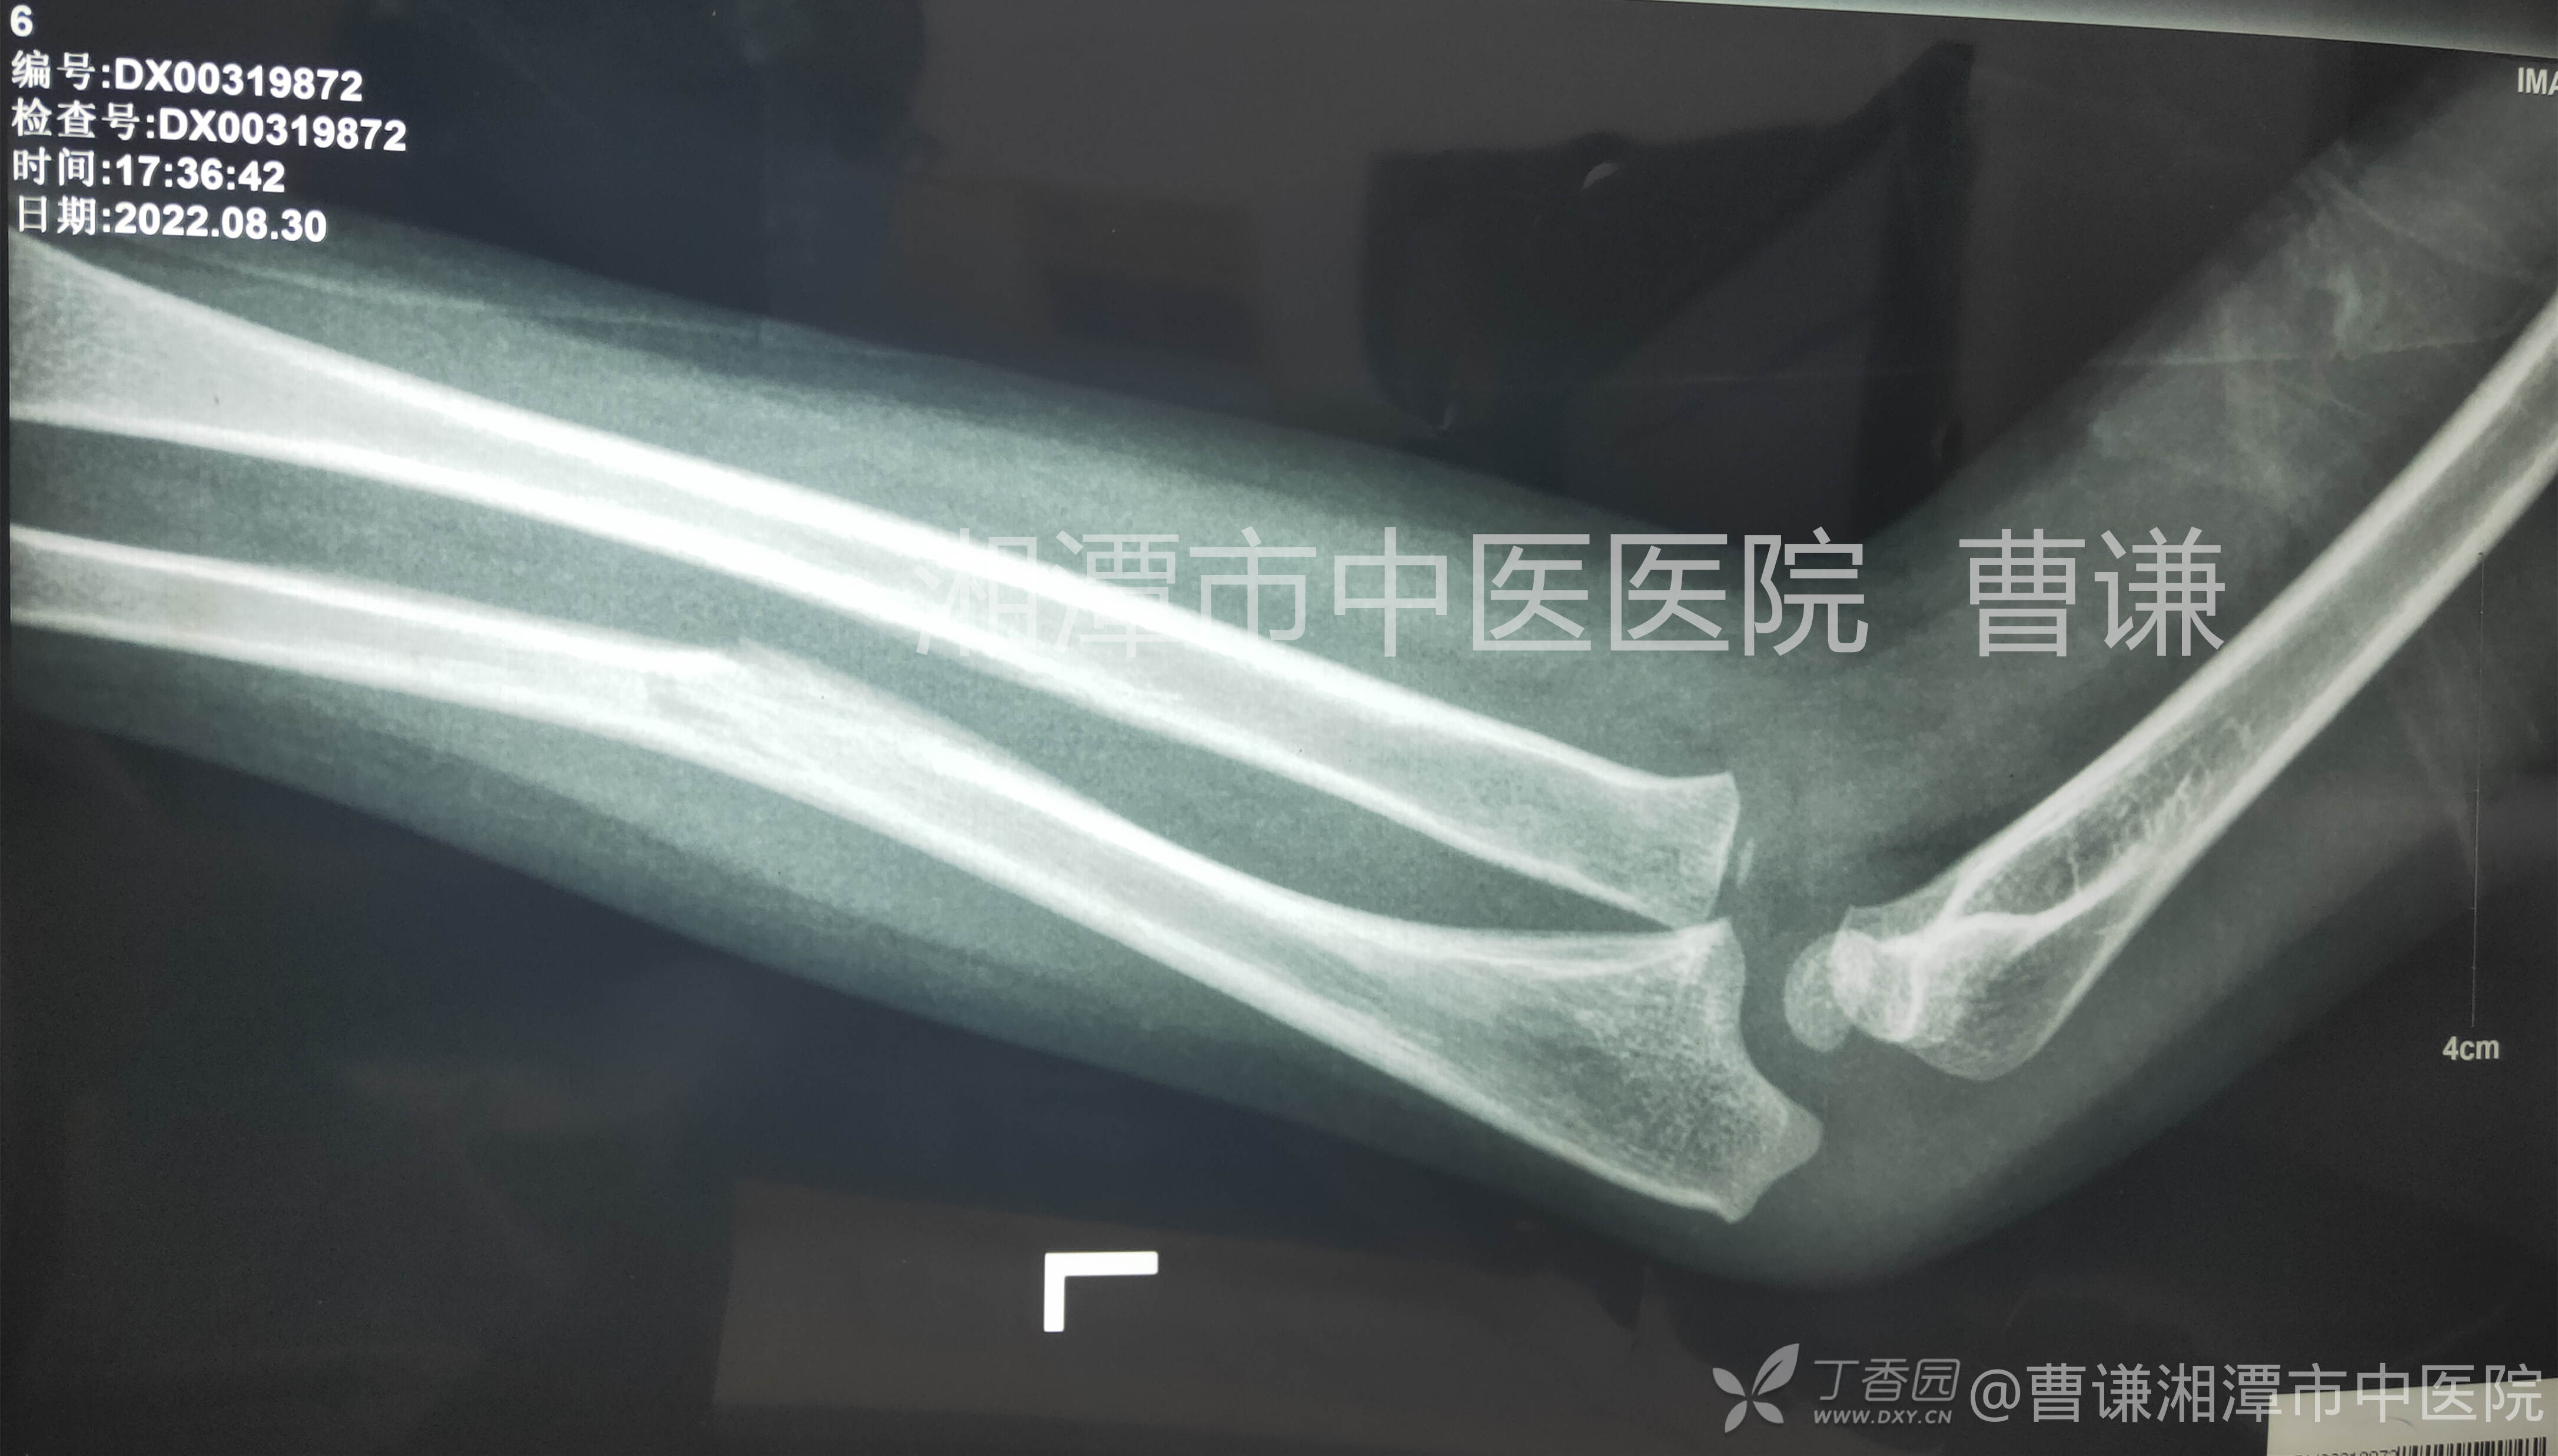

患者外伤后就诊于当地医院拍片检查示:左尺骨中段骨折,桡骨头脱位,当地医生予以手法复位石膏外固定。

这是伤后4天复查的X线片,显示尺骨中段骨折,仍有向前成角畸形,虽然有石膏伪影遮挡,还是可以看出肱桡关系匹配不良。